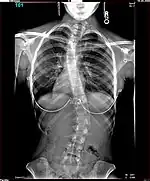

Polio patients would sometimes develop scoliosis, a condition where the spine becomes curved laterally (from side to side).[5] Harrington realised that existing treatments for scoliosis, which relied heavily on physical therapy, were inappropriate for patients paralysed by polio, and began to research new treatments. An early method he tried for scoliotic polio patients was manual correction of the scoliotic deformity at the time of surgery, and internal fixation of each facet. There were some benefits to this treatment but Harrington found that the fixation would not hold.[4] The hooks and threaded rods used would corrode and break, causing curvature to return to the spine. Two patients of this procedure died.[5]

The Harrington Rod, or Harrington implant, is a device for the straightening of the spine inside the body, designed by Paul Harrington. The device consists of a stainless steel rod, attached to the spine at the top and bottom of the curve with hooks. Attached ratchets are then tightened to distract or straighten the spine. Following surgery to insert the rod, the patient wears a postoperative plaster cast or brace for a few months, until vertebral fusion has occurred, after which the cast or brace is removed.[5]